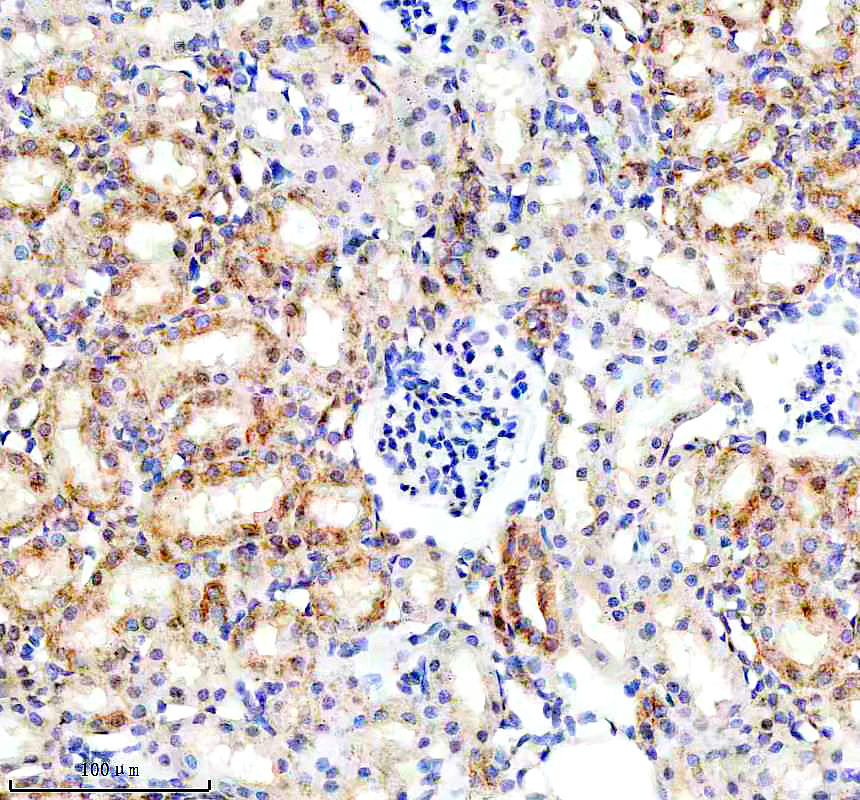

IHC analysis of BNIP3L using anti-BNIP3L antibody (BM5174) .

BNIP3L was detected in a paraffin-embedded section of rat kidney tissue. The tissue section was incubated with rabbit anti-BNIP3L Antibody (BM5174) at a dilution of 1:200 and developed using HRP Conjugated Rabbit IgG Super Vision Assay Kit (Catalog # SV0002) with DAB (Catalog # AR1027) as the chromogen.

IHC analysis of BNIP3L using anti-BNIP3L antibody (BM5174) .

BNIP3L was detected in a paraffin-embedded section of rat kidney tissue. The tissue section was incubated with rabbit anti-BNIP3L Antibody (BM5174) at a dilution of 1:200 and developed using HRP Conjugated Rabbit IgG Super Vision Assay Kit (Catalog # SV0002) with DAB (Catalog # AR1027) as the chromogen.